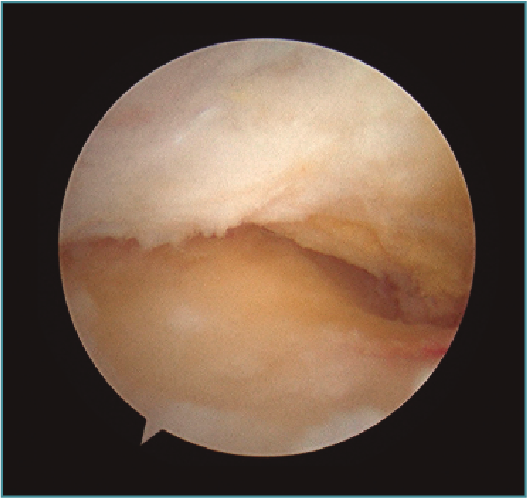

La gotiera externa está delimitada anteriormente por la articulación radiocapitelar y se presenta una visualización directa de la parte posterior del capitellum (Figura 19), común localización de lesiones osteocondrales(14).

Posterolateralmente, se delimita por la cápsula articular y superficial el ligamento colateral lateral(4), medialmente por el cúbito y la articulación ulno-humeral, y distalmente por el repliegue sinovial capsular que cubre la porción posterior del ligamento anular.

Existe un repliegue sinovial de tamaño y grosor variable, también llamado plica posterolateral o meniscoide (Figura 20), que va de la cápsula articular al ligamento anular y se continúa anterolateralmente con la plica anterior. Esta plica posterolateral se proyecta en forma de borde libre en el espacio entre el capitellum y la cabeza radial. En caso de ser hipertrófica e interponerse durante la extensión en el espacio entre cabeza radial y capitellum, puede producir síntomas dolorosos y erosiones condrales radiocapitelares(15).

Figura 19. La pared anterior de la gotiera lateral con capitellum posterior, cabeza radial y olécranon. Codo derecho, visión con óptica de 30° desde portal posterolateral.